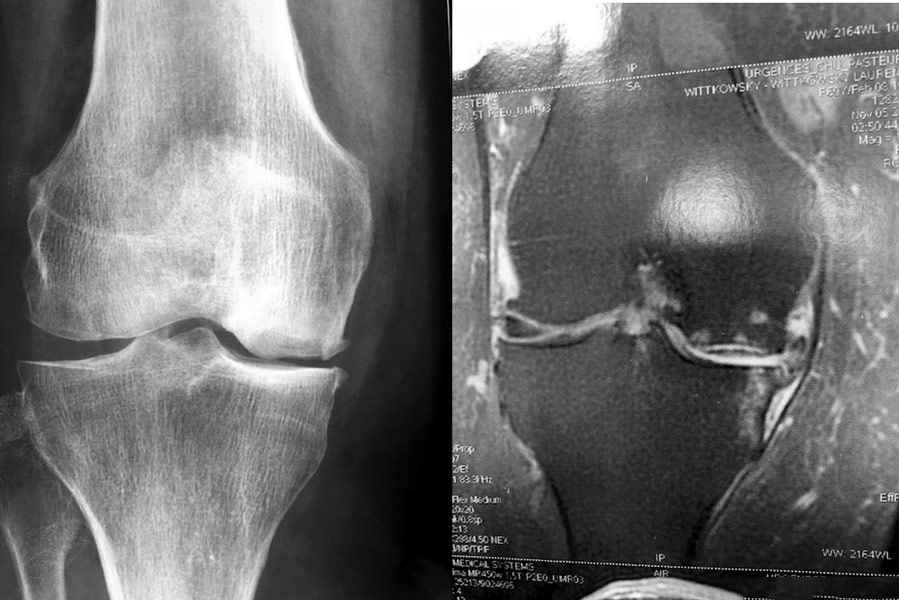

Arthrose interne isolée (pincement à la radio), Homme, 60 ans.

Arthrose interne (pincement à la radio) associée à une nécrose du condyle fémoral interne (visible à l’IRM). Homme, 65 ans.